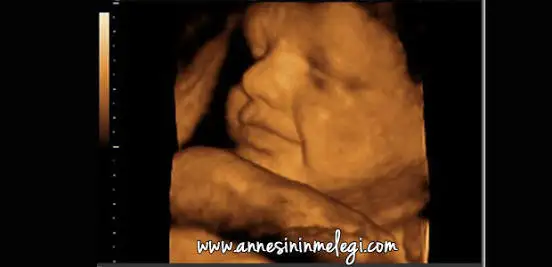

3 boyutlu goruntulerden bahsediyorum

benim zamanımda yoktu 3 boyutlu hoş olsada onlarıda birşeye benzetemezdim muhtemelen.. ben bebek memek göremiyorum millet ağzını burnunu görüyor benim dediğim buydu..

yok yahuu o koca burunlu benim olur mu googledan buldumSeninmi bu bebek masallah

Ay bumu koca burunlu cok tatliş :)yok yahuu o koca burunlu benim olur mu googledan buldum![]()